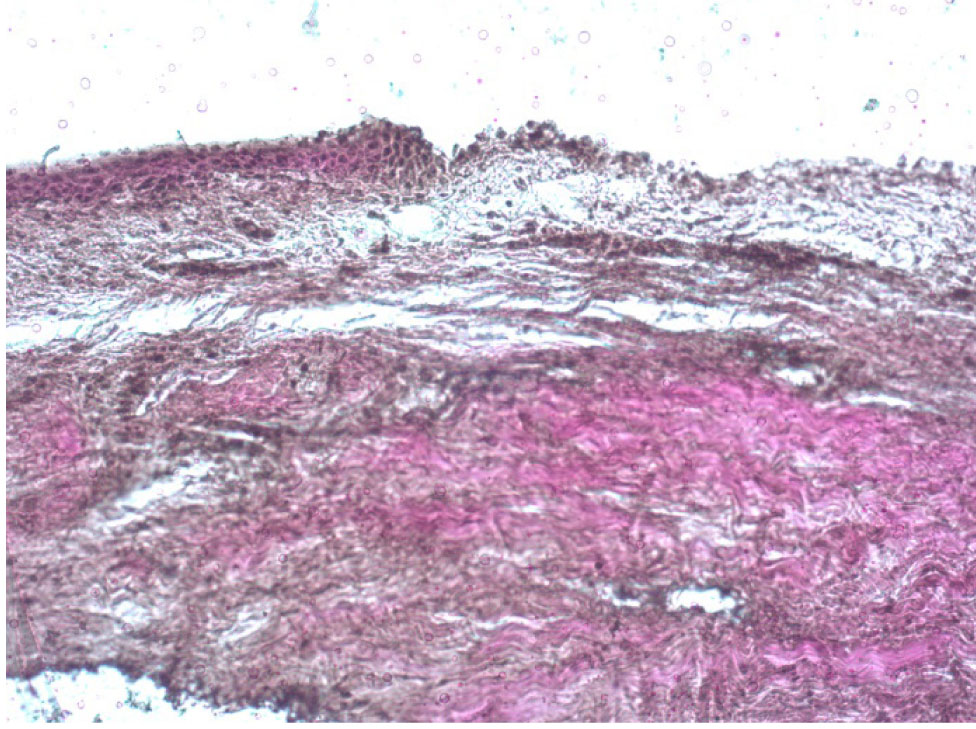

В первой группе в эксперименте полностью удалялся передний эпителий роговицы в зоне диаметром 8,0 мм. В препаратах роговицы, окрашенных по Ван Гизону, при полном отсутствии эпителия наблюдалось сохранение боуменовой мембраны в виде поверхностной гомогенной пластинки, в поверхностной строме – разобщение пучков коллагеновых волокон, появление обширных сливных межламеллярных лакунарных пространств между передней и средней стромой. При этом в толще средней и задней стромы наблюдались явления отека, инфильтрации ткани (рис. 5).

Рис. 5. Роговица свиного кадаверного глаза после полной механической деэпителизации, окраска по Ван Гизону, об. ×10

Рис. 7. Интактная роговица свиного кадаверного глаза, окраска по Ван Гизону, об. ×10

В группе интактных роговиц в препаратах визуализировались как сохранный эпителий с единичными мелкими зонами десквамации поверхностных слоев клеток, боуменова мембрана и стромальный слой с явлениями отека и набухания, но без наличия лакун между волокнами коллагена, что говорит о том, что интактный эпителий препятствует проникновению раствора рибофлавина в строму роговицы (рис. 7).